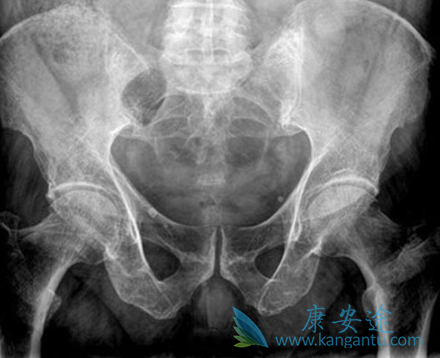

多发性骨髓瘤的病情发展的速度是较为缓慢,有很多患者在病情发展的早期并不能够发现病情,等到发展的后期有很多患者会出现骨痛,这种状况之下到医院进行检查,那么病情已经是非常严重的了,因为早期的症状不太明显,到医院进行检查的时候,会发现血沉加快,血液当中的免疫球蛋白有明显的异常,这个时候患者就要引起足够的重视。早期多发性骨髓瘤发生骨骼就会出现损伤这也是非常典型的症状,通过x射线检查的时候我们可以发现会有尼慢性的骨质疏松,同时会出现病理性的骨折,或者一些患者出现骨质硬化等等非常常见的症状。